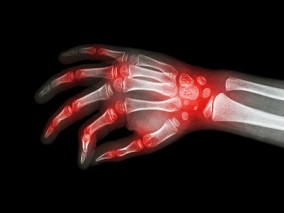

1小时条评论骨侵蚀是严重痛风患者结构性关节损伤的最常见特征,导致关节畸形和残疾。2022年6月,新西兰学者发表在《Arthritis Rheumatol》的一项随机、双盲对照试验,考察了口服降尿酸治疗侵蚀性痛风患者的强化血清尿酸降低...

1小时条评论46岁女性,1年前无明显诱因出现对称性多关节肿痛、晨僵,以小关节受累为主,3个月前关节肿痛程度较前加重,并伴有皮下结节。其母亲患有类风湿关节炎。如何制定诊疗计划? 主诉:对称性多关节肿痛1年,加重3个月。 ...